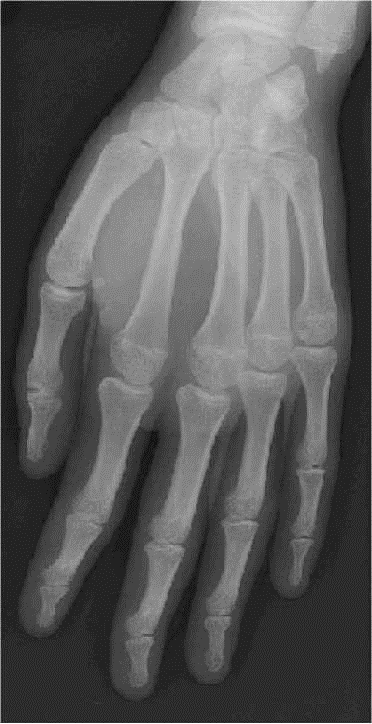

OBLIQUE

Ou 3/4

– – Assis de la même manière

– – Inclinaison de 45° de la face palmaire de la main par rapport au plan d’appui

– – Maintenir la main semi-abduction avec une cale

– – Centré sur la tête du 3ème méta

CRITERES DE REUSSITE

– – Vue en totalité de la main

– – Doigts bien individualisés

– – Seuls les métas sont à peine superposés

– – Différenciation Corticale/Médullaire (C/M) ANATOMIE RADIOLOGIQUE

IMAGE NORMALE